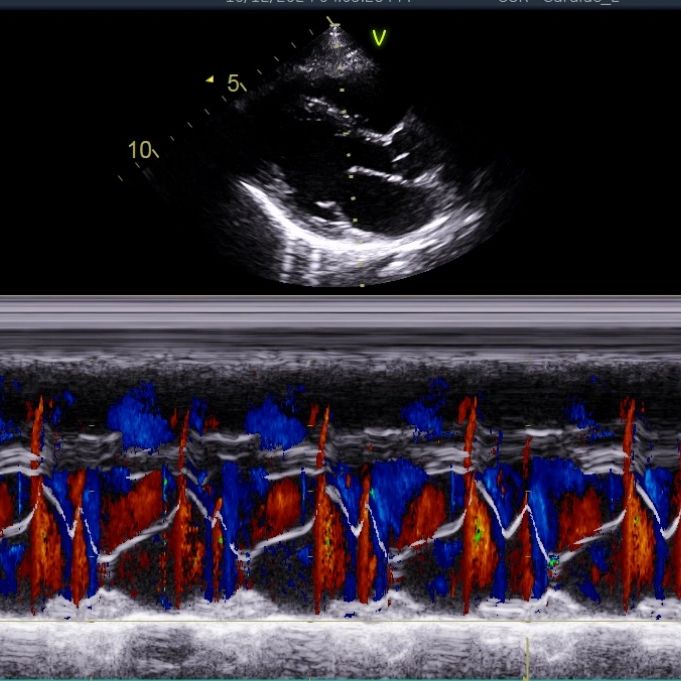

Evaluación del tamaño, función y válvulas del corazón mediante ultrasonido.